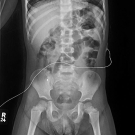

A 2-year-old otherwise healthy girl presented to a hospital emergency department with 2 days of worsening oral intolerance, worsening nonspecific abdominal pain, and nonbilious nonbloody vomiting.